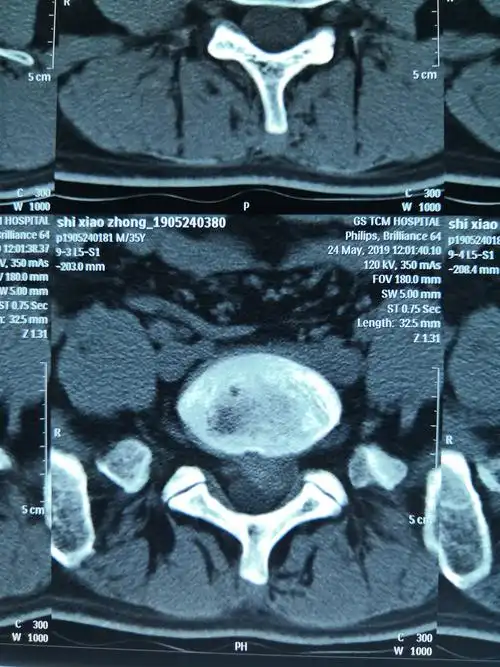

腰椎间盘ct平扫(l5-s1)